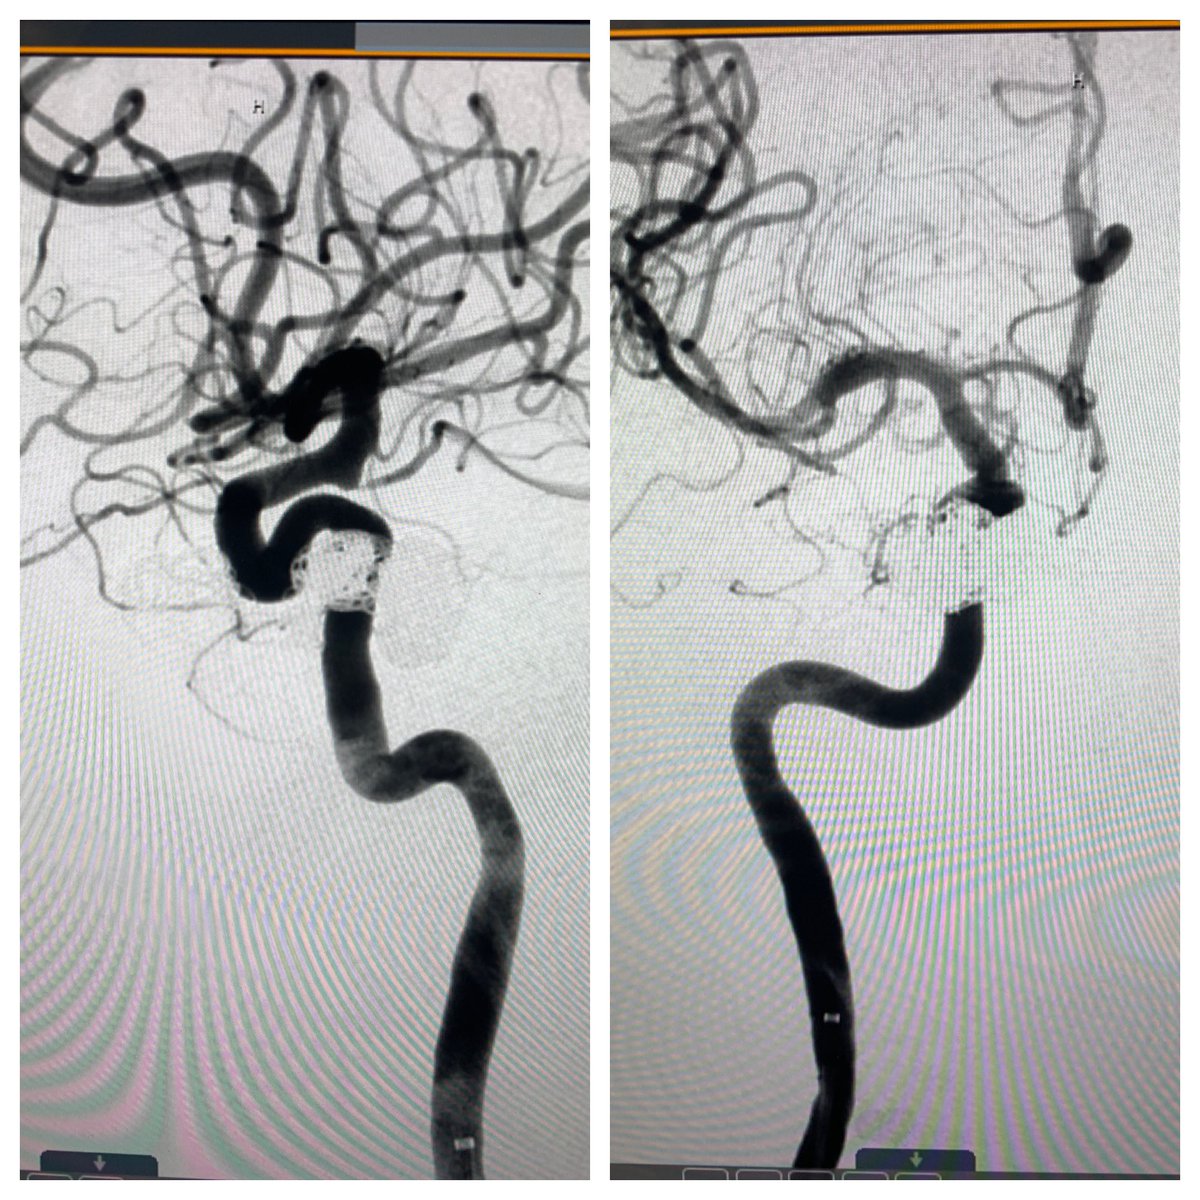

We are so focused on radial ARTERY access, why make venous access more streamlined for patients? Direct CCF a few weeks after MVC Sheaths in distal radial and AC stick into basilic vein Coils in cav sinus transvenous with balloon inflated TRA in ICA

#RadialFirst#RadialforNeuropic.twitter.com/Ydz0KCzjHp